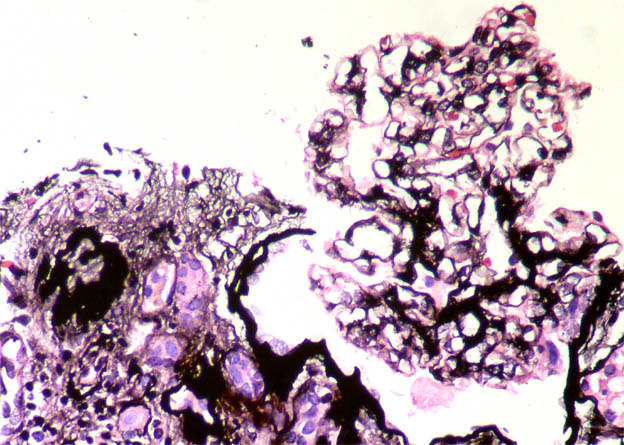

The patient is a 11-year-old boy with a history of steroid-resistant nephrotic syndrome since he was 7 years old. Renal biopsy at 8 years was diagnosed as focal segmental glomerulosclerosis (in another center, we do not have histological images). He continues with nephrotic syndrome since and now the serum creatinine has increased: 1.4 mg/dL. A new renal biopsy is undertaken to see the severity of the histological changes and decide whether to try another immunosuppressant treatment.

See the images of the second renal biopsy.

Figure 7. Methenamine-silver, X400.